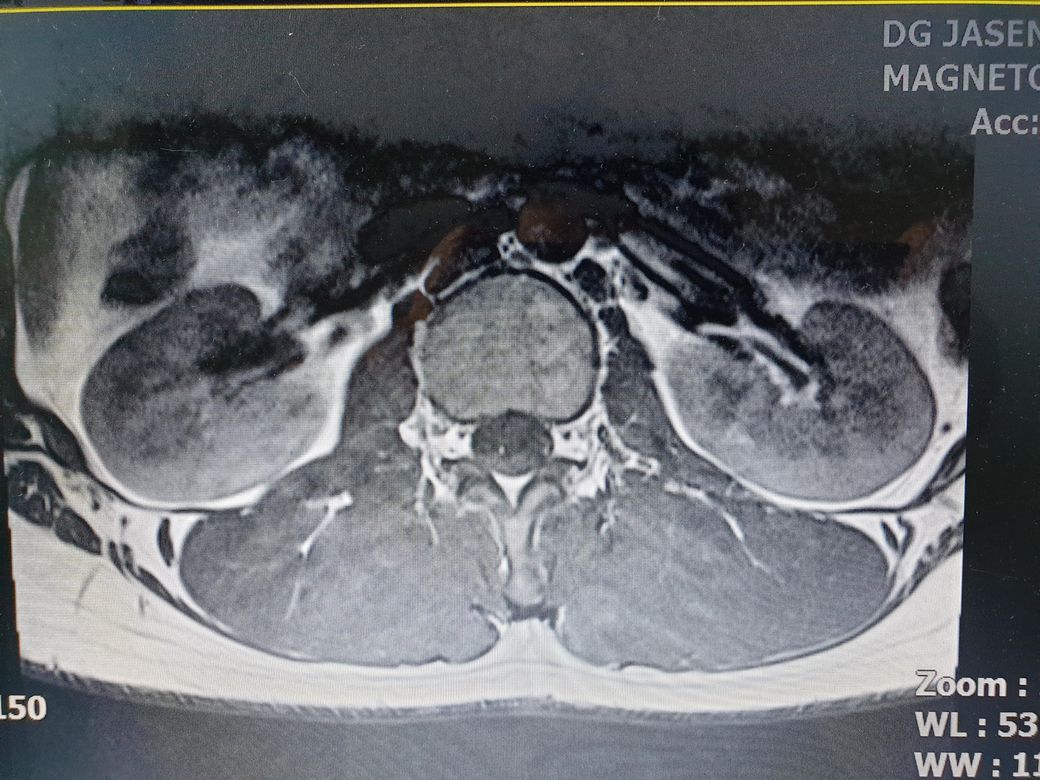

• 2번 째 사진

하지만 보여주신 sagittal view 만 봐서는 이렇게 튀어나간 디스크가 신경의 뿌리를 누르는지 아닌지 알아볼 수 없습니다. transverse view응 함께 봐야합니다.